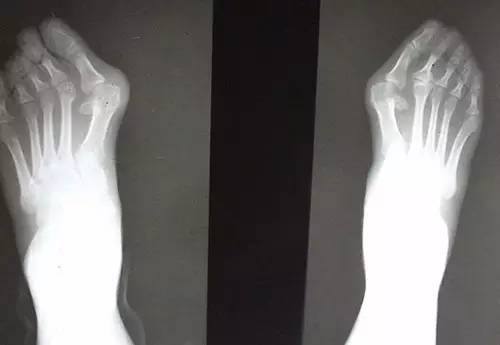

长期穿高跟鞋的双脚